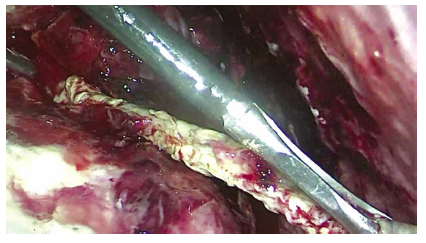

Se solicita una tomografía abdominal que revela una gran colección intraabdominal en el hemiabdomen derecho (Figura 1); se decide la laparoscopía exploratoria en la que se encuentra un absceso gigante intraabdominal de 750 cc (Figuras 2 y 3), que va desde el reborde inferior del hígado hasta el fondo de saco de Douglas. Se toma muestra para cultivo y se drena. Un útero aumentado de tamaño con fibrina en sus paredes, edema y eritema severo en la trompa derecha, revisando con azul de metileno para verificar su permeabilidad. Se encuentra el apéndice cecal en fase necrosada y perforada (Figura 4), el cual se extrae. Posteriormente se realiza el lavado peritoneal con 6.000 cc de solución salina normal (Figura 5). Se deja drenaje en fondo de saco de Douglas (Figura 6). El tiempo de hospitalización y el manejo antibiótico con piperacilina tazobactam fue de 10 días. El reporte del cultivo fue Escherichia coli.